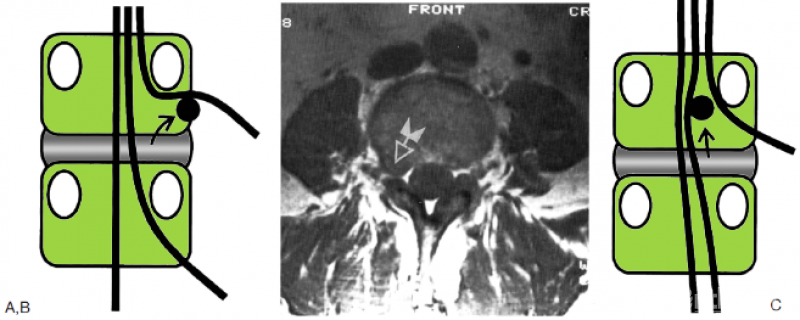

图18.10 A:图示为第2层的椎间盘突出,以椎间孔内的突出最为常见。箭头所示为椎间盘突出的移位路径;B:T1加权轴位MRI显示L3右侧椎间孔内的椎间盘突出(箭头);C:罕见的第2层椎间盘突出,位于椎管内。箭头所示为椎间盘突出的移位路径;D:T1加权轴位(上图)和矢状位(左下图)以及梯度回波矢状位(右下图)MRI显示第2层椎间盘突出